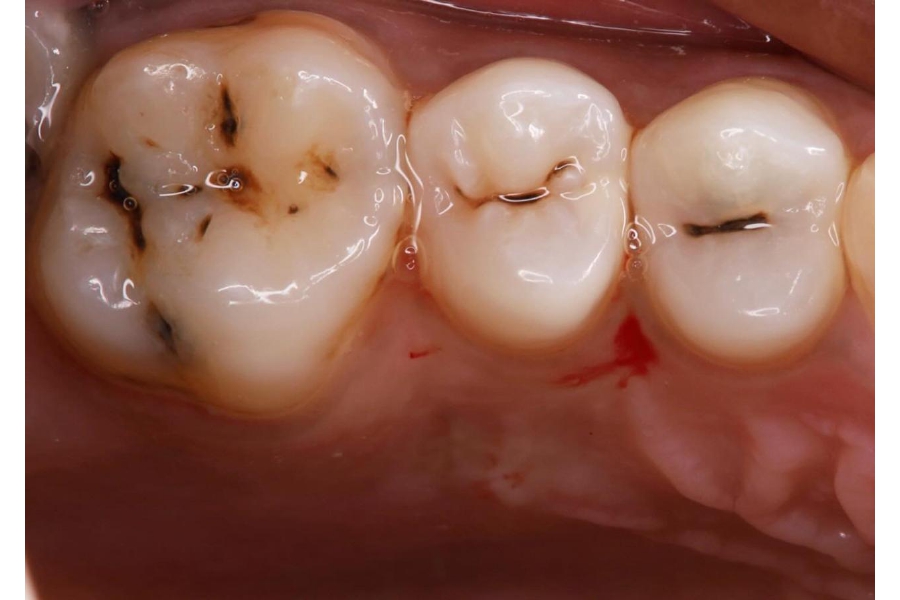

علامة مبكرة على تسوّس يحتاج علاجًا محافظًا قبل أن يتعمّق.

مؤشر على فقدان مينا/عاج يتطلّب تنظيفًا وحشوًا تجميليًا.

قد يدل على فجوات تسوّسية بينية تحتاج ترميمًا وضبط تلامس الأسنان.